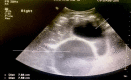

Figure 1. Abdominal ultrasound

The short white arrow shows the distended gallbladder, and the long white arrow shows the cyst measuring about 7.8 x 7.6 cm.